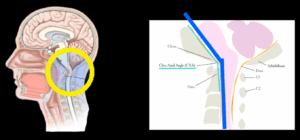

最近の研究では、メニエール病症状の背景に頭蓋頸椎角度異常が潜んでいる可能性が報告されています。

頭蓋内圧や脳圧の亢進、または頭蓋内高血圧の症状をお持ちの方が頻繁に来院されています。目の奥から頭痛が発生したり、心臓の鼓動に合わせて聞こえる拍動性耳鳴りがあったり、悪心、嘔吐、めまいを訴えられます。一晩中横になっている姿勢では脳浮腫がさらに悪化する可能性があるため、朝起きる時に頭痛があり、咳をする時や頭を下げる時のように頭蓋内圧を増加させる行為によって頭痛がさらに悪化するともおっしゃいます。また、首、肩、背中部位の痛みが多く、視神経浮腫による羞明や目のかすみといった眼症状を伴い、耳鳴り、ジストニア、斜頸、後頸部痛などの症状を訴えられます。